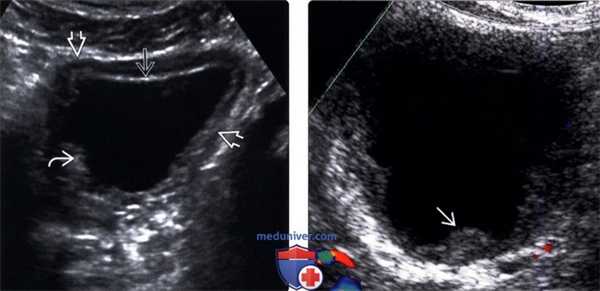

(Левый) На косопоперечном трансабдоминальном ультразвуковом срезе мочевого пузыря у этого пациента с ранее диагностированным туберкулезом МПТ визуализируется диффузное утолщение стенки пузыря; слизистая гиперэхогенная вероятно, вследствие кальцификаци, и имеет неровные контуры.

(Правый) На продольном ультразвуковом срезе визуализируется мочевой пузырь при туберкулезе. Имеется неравномерное утолщение слизистой около отверстия мочеточника — наиболее ранний признак начала заболевания.